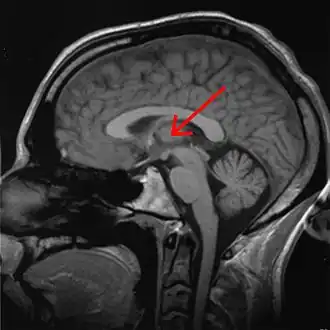

Таламус на МРТ

Тала́мус, иногда — зри́тельные бугры (лат. Thalamus; от др.-греч. θάλαμος — «камера, комната, отсек») — большая масса серого вещества в верхней части таламической области промежуточного мозга хордовых животных, в том числе и человека. Впервые описан древнегреческим врачом и анатомом Галеном. Таламус — это парная структура, состоящая из двух половинок, симметричных относительно межполушарной плоскости. Таламус находится глубже структур большого мозга, в частности коры или плаща. Под таламусом расположены структуры среднего мозга. Срединная (медиальная) поверхность обеих половинок таламуса одновременно является верхней боковой стенкой третьего желудочка головного мозга.

Таламус выполняет несколько важных физиологических функций. Он отвечает за передачу сенсорной и двигательной информации от органов чувств (кроме информации от органов обоняния) к соответствующим областям коры больших полушарий млекопитающих или плаща мозга низших хордовых. Таламус играет важную роль в регуляции уровня сознания, процессов сна и бодрствования, концентрации внимания.